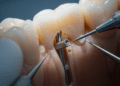

Conhecer a anatomia do dente é fundamental para o diagnóstico, tratamento e prevenção de doenças bucais. Procedimentos como obturações, canal radicular, próteses e ortodontia dependem do entendimento claro das características estruturais para serem eficazes.

Além disso, a anatomia dentária é essencial para a identificação dos dentes e suas funções, auxiliando o profissional na escolha de técnicas e materiais adequados segundo cada caso clínico.